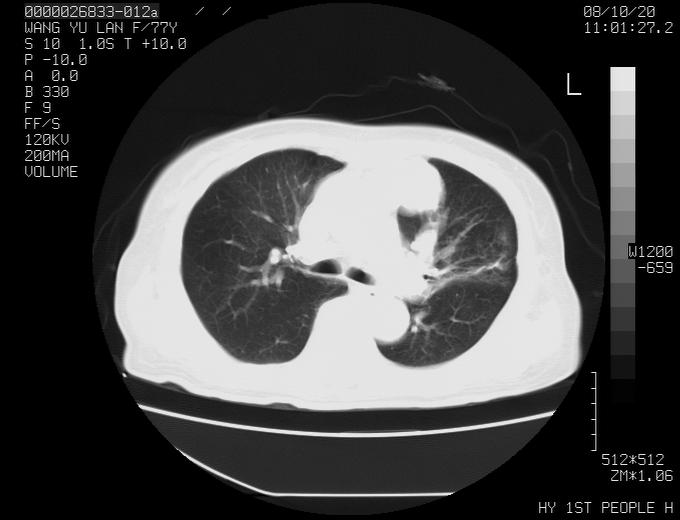

女性,77岁,胸部疼痛半月。左上肺团块影,本人考虑血管畸形,请分析

非常典型的avm(谢谢楼主,收藏了)

左上叶前段多发结节肿块并前段支气管息肉样结节、上叶腋亚段阻塞性肺炎,以结核可能性大。

纵隔有多个淋巴结肿大,提示周围型肺癌并转移可能性大。

动脉期未见大血管同步强化,首先考虑周围型肺癌

1、考虑avm可能性大。2、纵隔有肿大淋巴结,左肺上叶有炎性病变,不排除肺癌并转移可能。